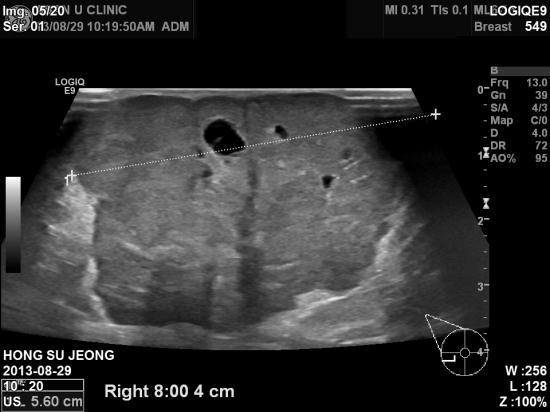

아산유외과 개원 후 21번째 유방암 진단.

3년동안 있던 유방에 혹이 피부바깥을 튀어나오며

커져 내원하셨다는 만 59세 여자분입니다.

조직검사로 우측 유방암의 피부, 우측 겨드랑이 전이를 확인하고

서울 아산병원전원하였습니다.